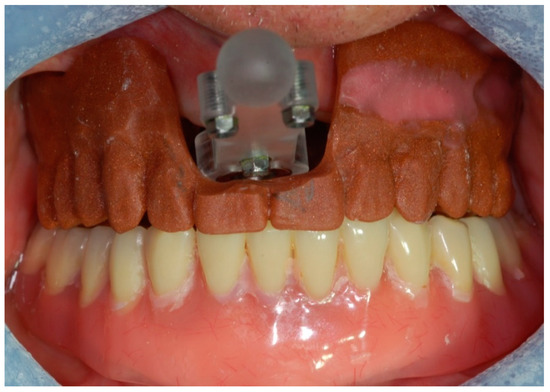

2. Case Report

3. Procedure

- Step 3. Image-to-patient registration via registration templates, external registration frames, or bone markers.